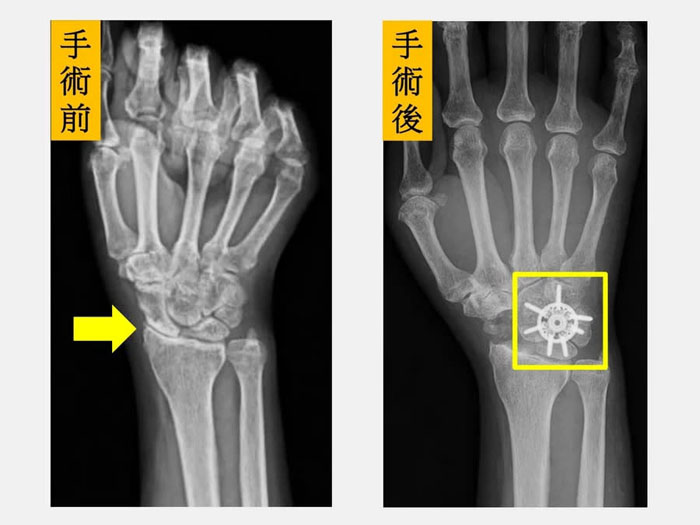

陈重宇表示,由于刘先生的症状是手腕肿胀、活动受限和握力明显下降,X光检查显示已进展至中后期病程,经医疗团队充分讨论后,刘先生接受“舟状骨切除合并四角融合术”(scaphoid excision and four corner fusion),并使用新型环状钢板固定,复原顺利。